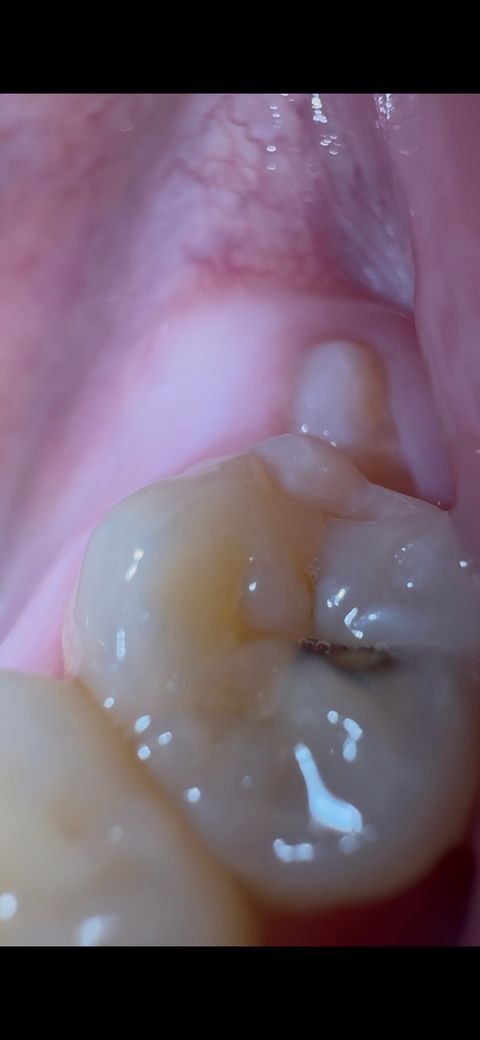

어금니에 충치 발생했습니다 당장 치료해야하나요

오른쪽 사랑니 나기 전 어금니 입니다

사진에서도 어금니 확인하실 수 있어요

충치 주변 치아가 안쪽에서 검은색을 띄는 것을 보니

꽤 진행된 충치인 것 같아서 걱정되네요